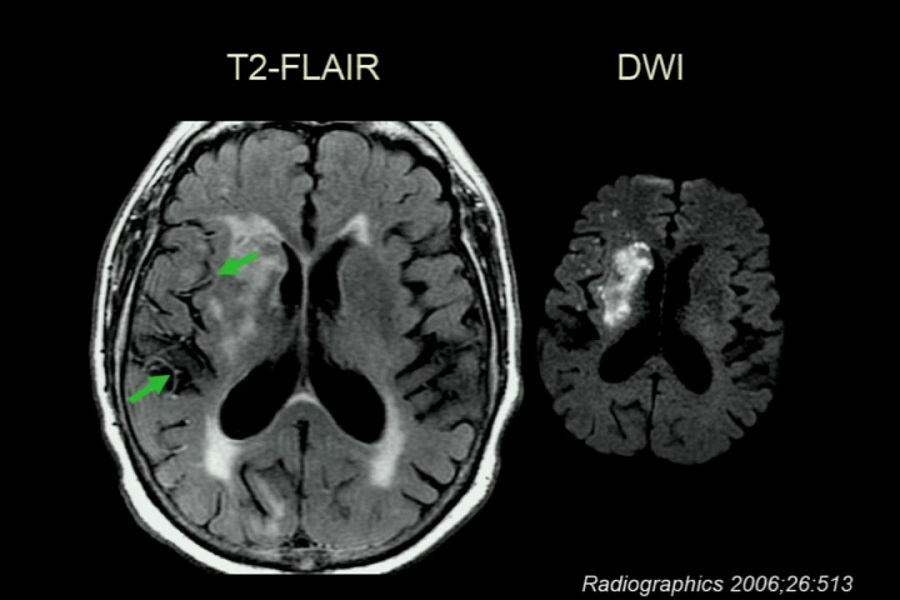

《医学放射科》2019年第3讲(总第104讲)基于病例学习神经影像学(3)

《医学放射科》2019年第1讲(总第102讲)基于病例学习神经影像学(1)